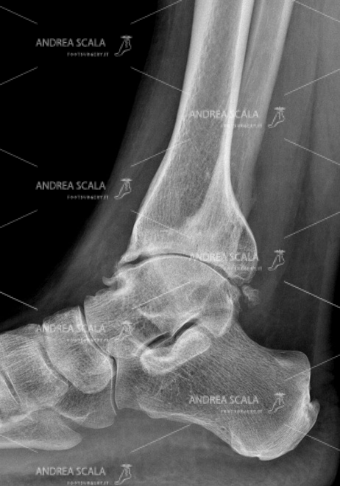

Si pensi che, addirittura, anche il solo atto di rimanere in piedi a lungo è una fonte di stress per l’arto che, col passare del tempo, diventa sempre più vulnerabile e quindi più facilmente soggetto a traumi. Per questo, quando un soggetto manifesta dolore oppure soffre di processi di artrosi degenerativi, il medico chirurgo ed ortopedico del piede può arrivare a consigliare un’operazione di protesi di caviglia.

Un intervento che permette di evitare che il dolore e la rigidità causati dal consumo incessante delle cartilagini peggiorino vorticosamente, arrivando a rendere difficile la normale deambulazione con serie conseguenze limitative sui movimenti ed invalidità. L’operazione, infatti, permette ai pazienti di riprendere le loro attività sin da subito, ovviamente con le dovute accortezze ed un piano di riabilitazione seguito passo passo con il proprio specialista.

In particolare, per un corretto montaggio della protesi, occorre rispettare l’anatomia della caviglia, facendo attenzione a conservare le parti anatomiche più delicate, come l’astragalo e i legamenti, nel modo migliore per evitare l’instabilità. In secondo luogo, poi, va rispettata anche la biomeccanica della caviglia, mantenendone l’allineamento. La protesi, infatti, viene stabilizzata ad ogni passo e non subisce carichi asimmetrici.